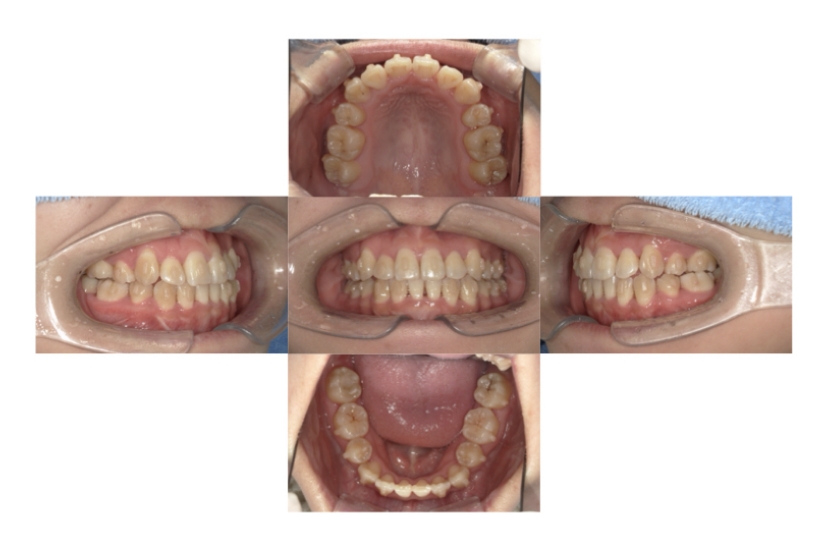

症例3

叢生

抜歯

ブラケット矯正

上下顎叢生(上下の前歯のガタガタ)のケースです。

装置はラビアル(上下表側)で、上下顎の小臼歯を4本抜歯を行っています。抜歯したスペースを使って、上下の前歯の後方移動と叢生(ガタガタ)の改善を行っています。

主訴 八重歯を治したい。

年齢・性別 25歳 女性

お住まいの地域 神奈川県川崎市

治療方針 抜歯スペースを利用して上前歯の叢生(ガタガタ)の改善

抜歯部位 上下顎左右第一小臼歯

使用装置 ラビアル(上下表側)、顎間ゴム

治療期間 1年11か月

治療回数 16回

リテーナー クリアリテーナー

BEFORE

AFTER